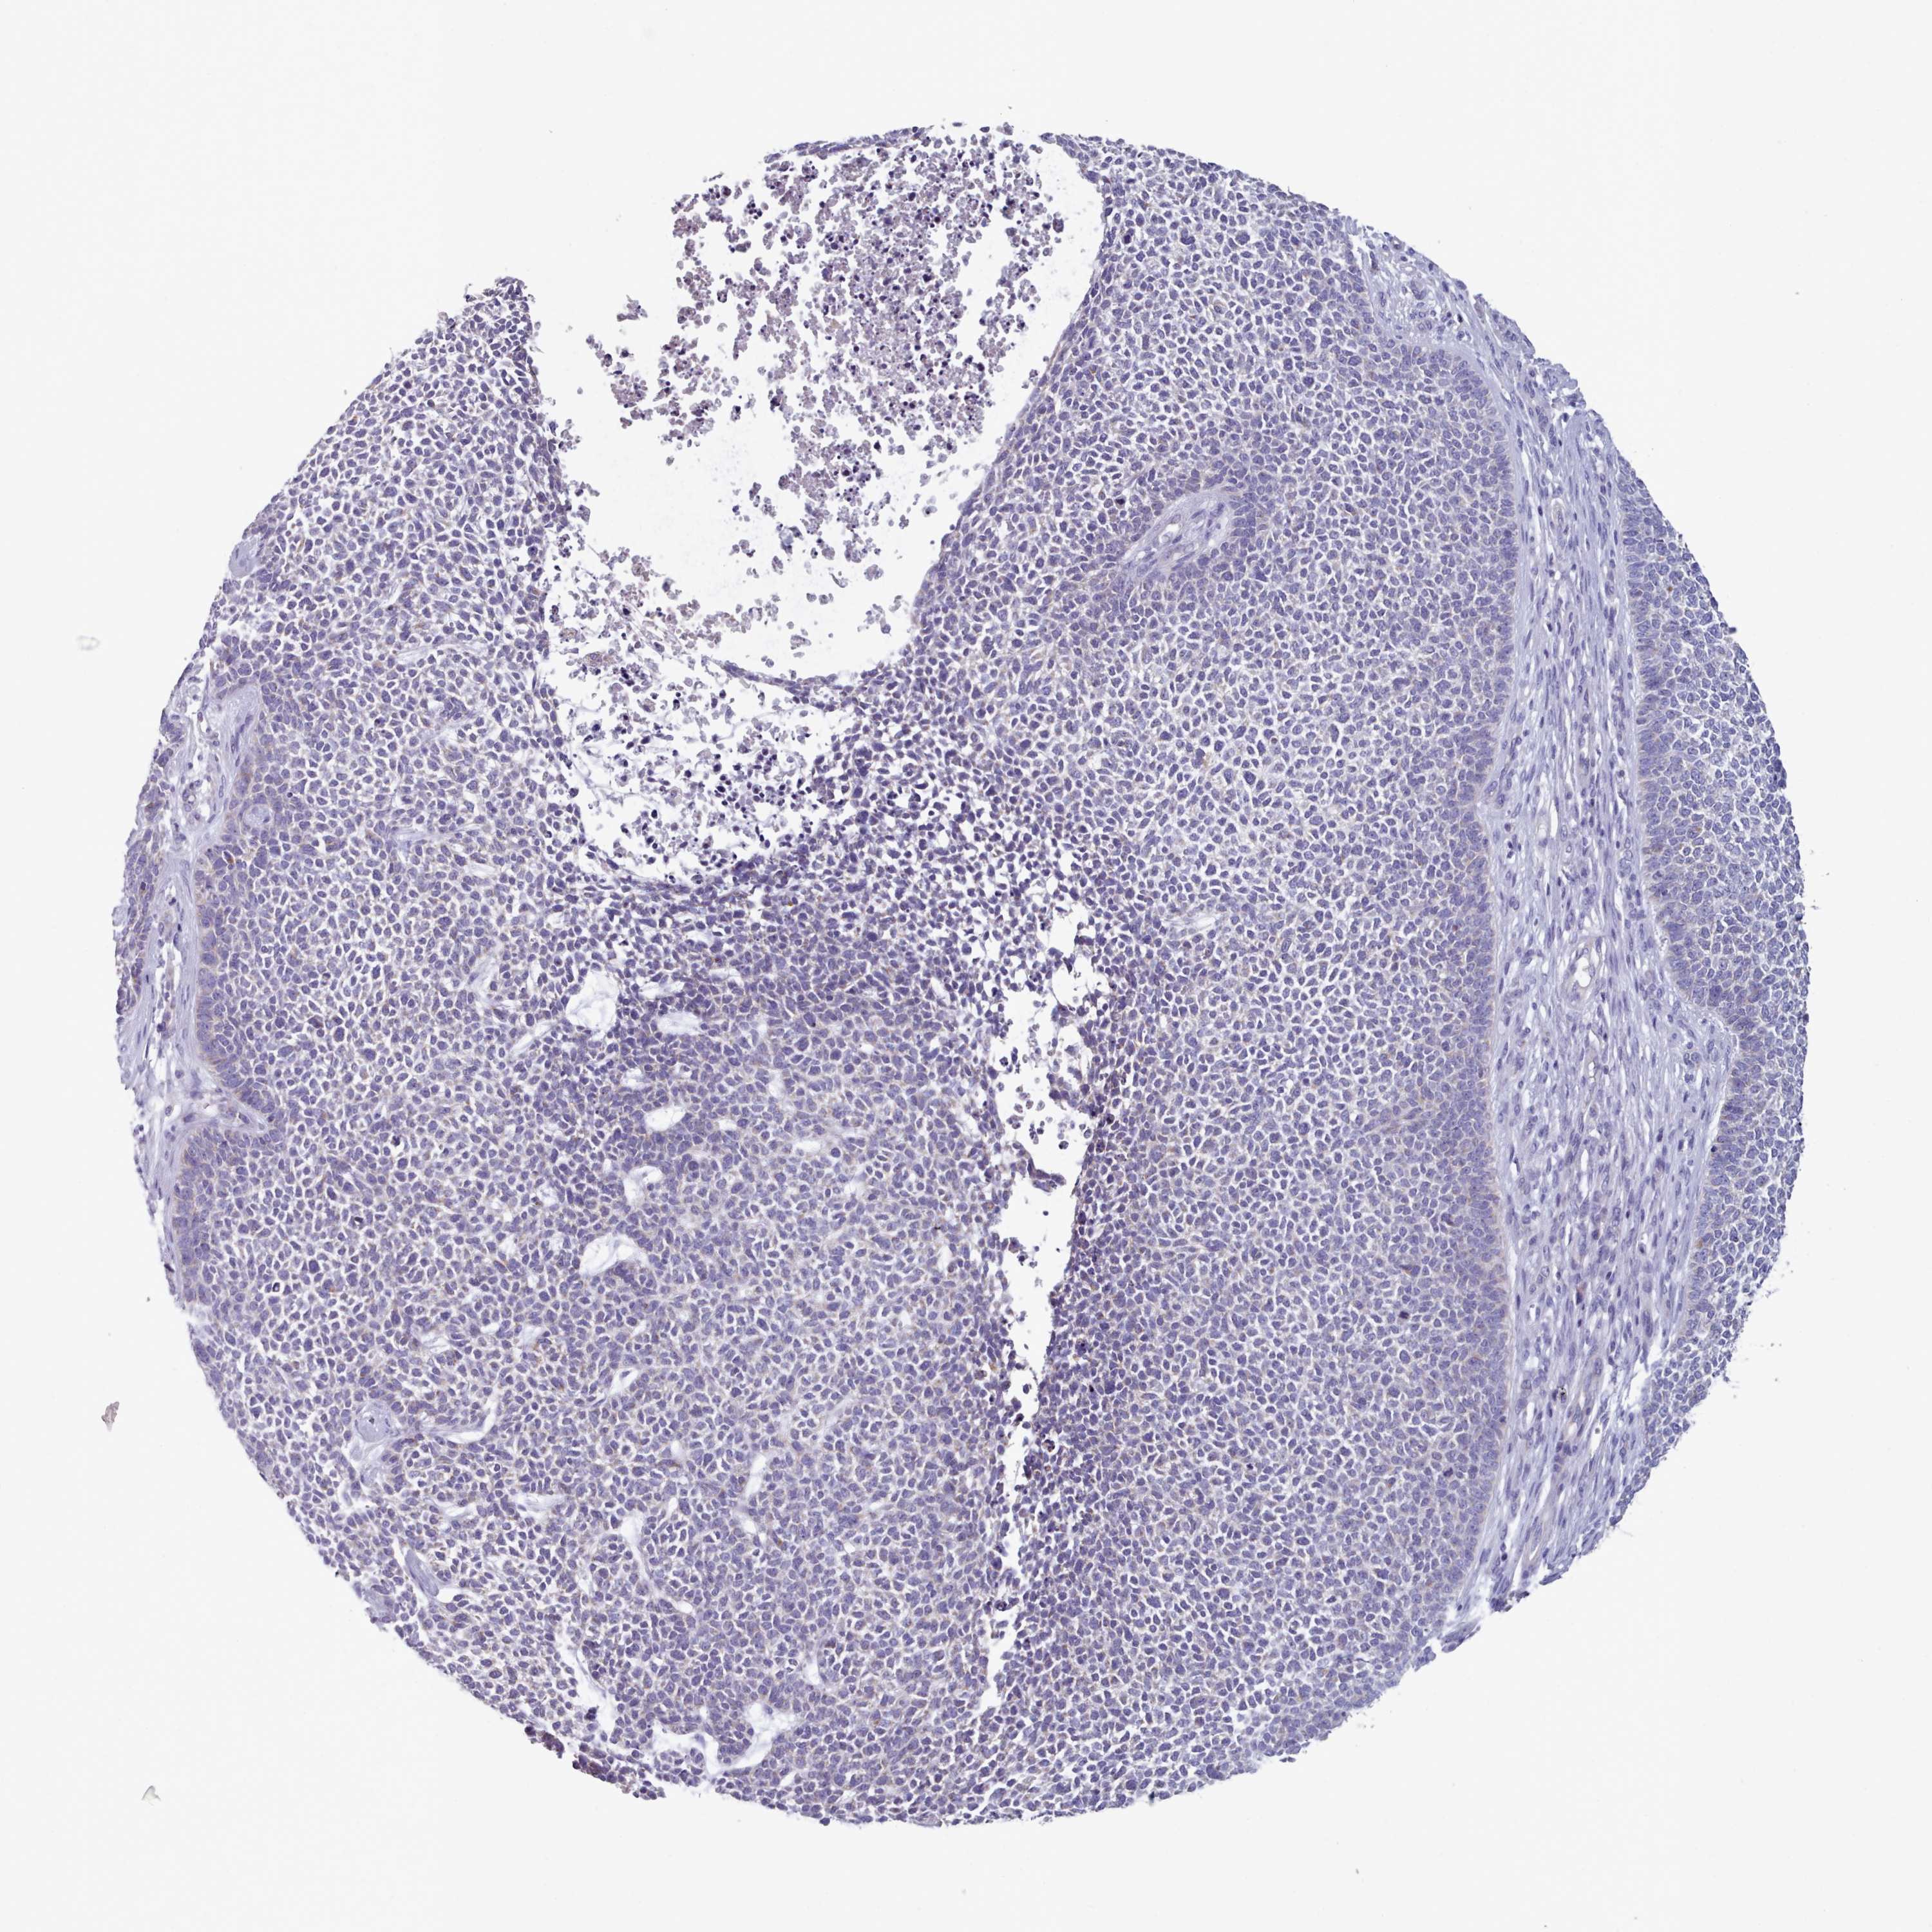

Basal cell and squamous cell cancer

SKIN CANCER - Protein expressioni

A mouse-over function shows sample information and annotation data. Click on an image to view it in a full screen mode. Samples can be filtered based on level of antibody staining by selecting one or several of the following categories: high, medium, low and not detected. The assay and annotation is described here.

Antibody stainingi

Antibody staining in the annotated cell types in the current human tissue is reported as not detected, low, medium, or high, based on conventional immunohistochemistry profiling in selected tissues. This score is based on the combination of the staining intensity and fraction of stained cells.

Each image is clickable and will lead to virtual microscopy that enables deeper exploration of all samples and also displays staining intensity scores, fraction scores and subcellular localization as well as patient and tissue information for each sample.

Antibody HPA049552

Antibody HPA072442

Staining

High

Medium

Low

Not detected

Intensity

Strong

Moderate

Weak

Negative

Quantity

>75%

75%-25%

<25%

None

Location

Nuclear

Cytoplasmic/membranous

Cytoplasmic/membranous,nuclear

Basal cell carcinoma

Squamous cell carcinoma, NOS

Squamous cell carcinoma, metastatic, NOS